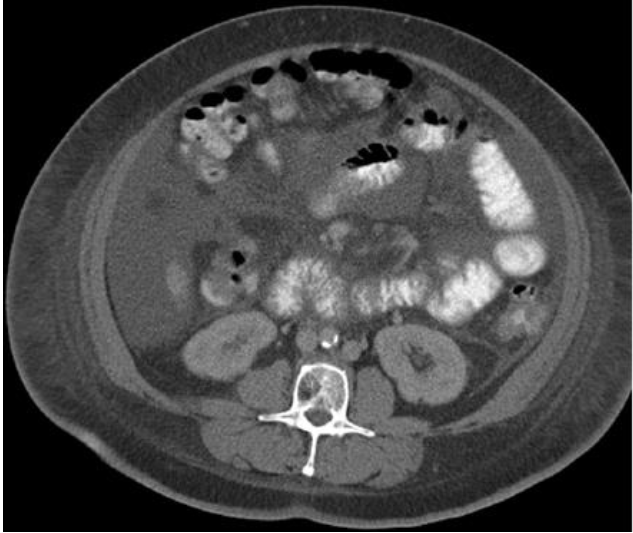

Be careful not to analyze organs that might be touching the skeletal muscle such as intestines, liver, or kidneys as muscle.

·If the color scheme tool does not allow the unknown structures to be adequately visualized, go back to the entire original series of images to see what those unknown structures might be. The best way to do this is to find the L3 image in the entire series of images and follow the structure downward and upward to help get a clearer picture of what it could be.